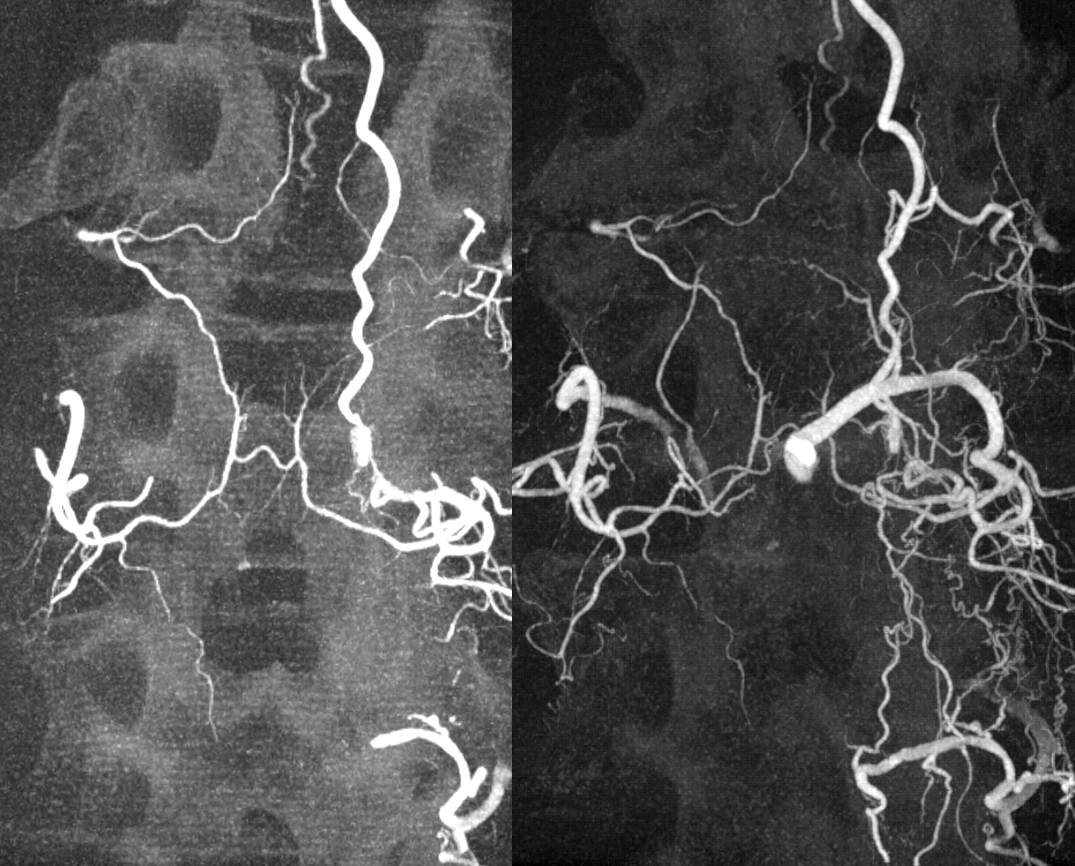

Key image here — injection of Adamkiewicz now shows return of the prodigal veins to the venous phase of the cord. Image on left also shows the now liberated basket.

pre and post Rx ASA views side by side

It is critical to understand cord venous drainage in post-dural fistula patients is never normal. The radicular veins are still missing. This may in part be responsible for the incomplete clinical recovery, although the main reason is probably cord damage before fistula occlusion.

Cone Beam CT shows nBCA cast in the fistula basket and radicular vein. Fusion of pre and post Rx CBCTs is nice

More cool fusions